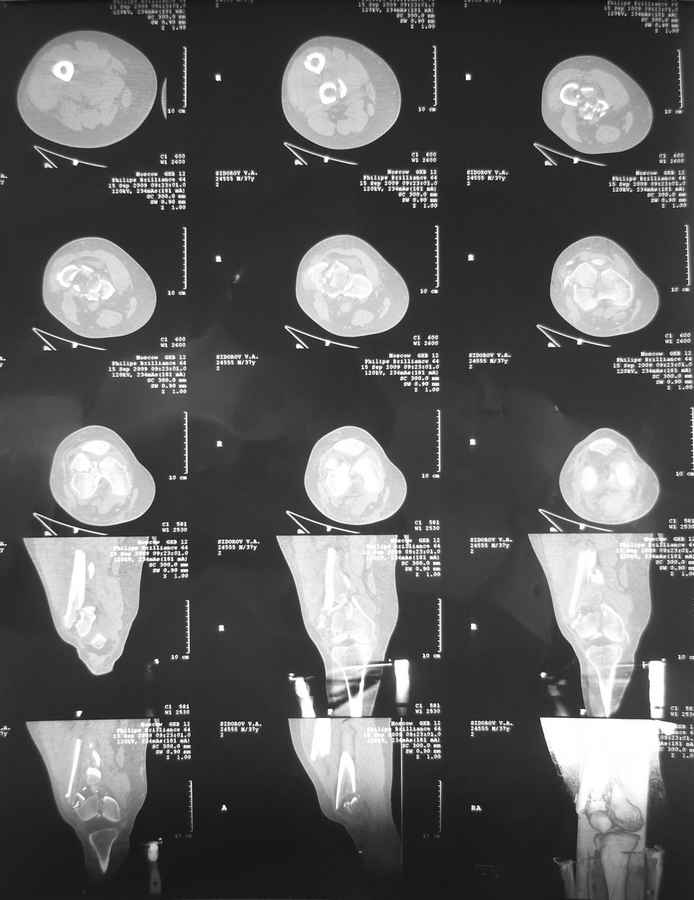

еще кт

я совсем молодой доктор так что без обид могу ошибаться во многом.

Это перелом не нижней трети, а дистального суставного конца, с распространением на диафиз. Что-то между C2 и C3. Но пока ближе к C2 по увиденному - вторую проекцию еще не показали.

На профиле стало видно, что открываться придется, это перелом C3, хотя можно назвать и C2+, т.е. с еще и фронтальным раскалыванием одного мыщелка. Надо сделать медиальную артротомию, ступеньку на внутреннем мыщелке устранить, ввести либо несколько временных спиц спереди назад, или сразу винт вдоль эллипса мыщелка. А дальше как выше написано - дистрактор, и штифтовать. Учитывая наличие открытого колена - вполне уместно ретроградно.